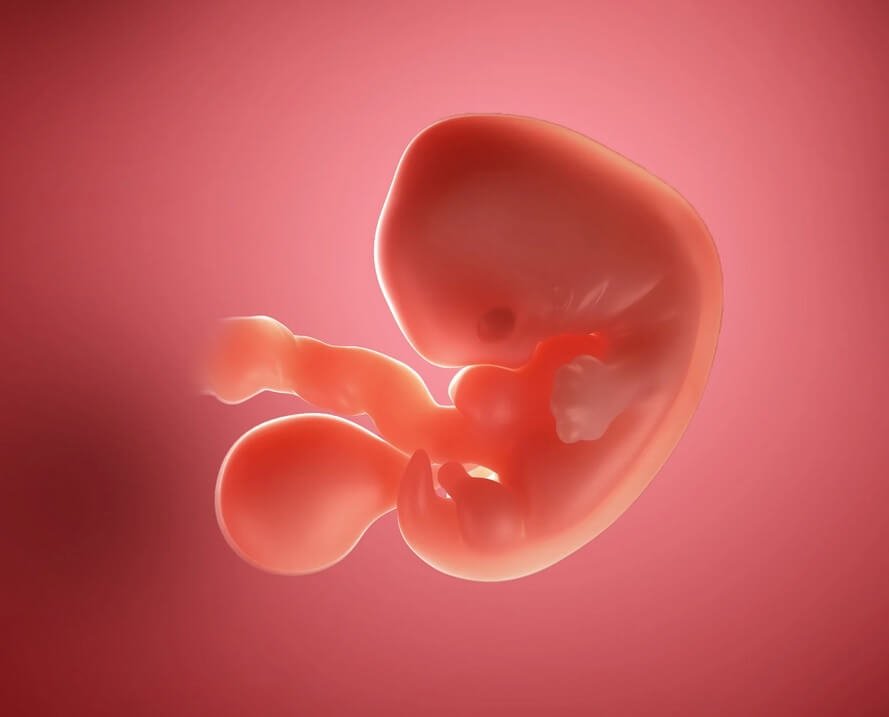

در هفته ششم بارداری، کودک شما تقریباً 1.8 – 1.4 اینچ طول دارد. تقریباً به اندازۀ یک دانه انار. او شبیه به یک بچه قورباغه به نظر می رسد. با یک دم کوچک که به ستون فقرات تبدیل خواهد شد. جوانه های ریزی در راه تبدیل شدن به دست، پا و گوش هستند. مغز، ریه ها و سایر اندام ها نیز در حال رشد هستند. اجزای صورت نیز در همین هفته شروع به شکل گیری می‌کند. دندان ها و یک لایه نازک از پوست وجود دارد. ضربان قلب کودک اغلب با سونوگرافی واژن در این مرحله از بارداری قابل تشخیص است.

در جایی که قلب تشکیل شده است، یک برآمدگی و در جایی که سر قرار دارد، یک حالت تحدب دیده می‌شود. دست و پاهای ریز شروع به شکل گیری می کنند و به عنوان جوانه اندام شناخته می شوند. رویان با لایه نازکی از پوست شفاف، پوشانده شده است. به طور کلی، در این زمان جنین شما هنوز شبیه به یک کودک نیست.